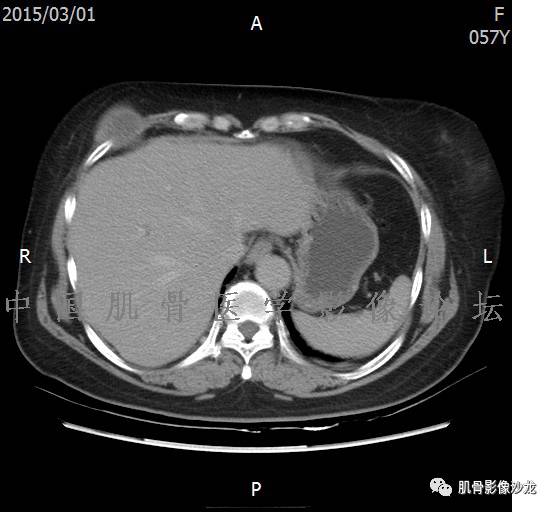

雪舞 :第二例,位于骶骨,有骨质破坏并有软组织肿块,软组织肿块边界清

雪舞: 第二例我们能够看到破坏与软组织肿块不成比例,软组织肿块大,破坏小

雪舞 :第二例挺难的,骨质破坏是溶骨性的,局部皮质中断,软组织肿块外缘光滑

雪舞 : 软骨肉瘤的发病率居原发性恶性骨肿瘤的第三位,其特点是肿瘤内具有软骨基质

雪舞:弓形钙化,钙化比例少于面积的1/3,钙化边缘模糊

雪舞 : 都是软骨肉瘤鉴别于内生软骨瘤有意义的区别点